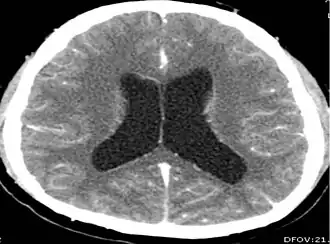

CT scans and magnetic resonance imaging (MRI) give objective information about the number and pattern of lesions, the stage of healing, and how the immune system is responding to the parasites.[19] MRIs are better for evaluating different spatial planes and provides clearer images, which helps in identifying small lesions at the back of the brain or near the skull that may be missed on CT scans. CT scans are more sensitive at detecting calcium buildup in the brain due to its ability detect calcifications in the brain.[30]

Live vesicular cysts are small, round lesions with little swelling around them and do not need contrast for imaging. The tapeworm head (scolex) usually appears as an asymmetric nodule inside the cysts. Multiple live cysts with these heads corroborate the diagnosis. Once the cysts begin to break down (colloid cysts), their borders become unclear, they are surrounded by swelling and exhibit significant ring or nodular contrast enhancement. Calcified cysticerci are shown on CT scans as non-enhancing hyperdense nodules without swelling.[20]